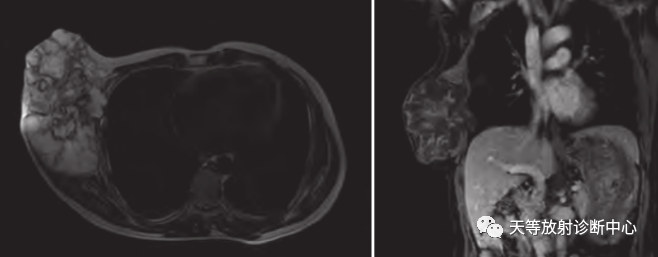

肿瘤复发,椎旁分叶状软组织肿块,内部信号不均,混杂信号,高低信号不等,内见线状小叶间隔。

DWI信号较高,内部钙化灶呈散在泥沙样低信号灶。

诊断软骨肉瘤复发。